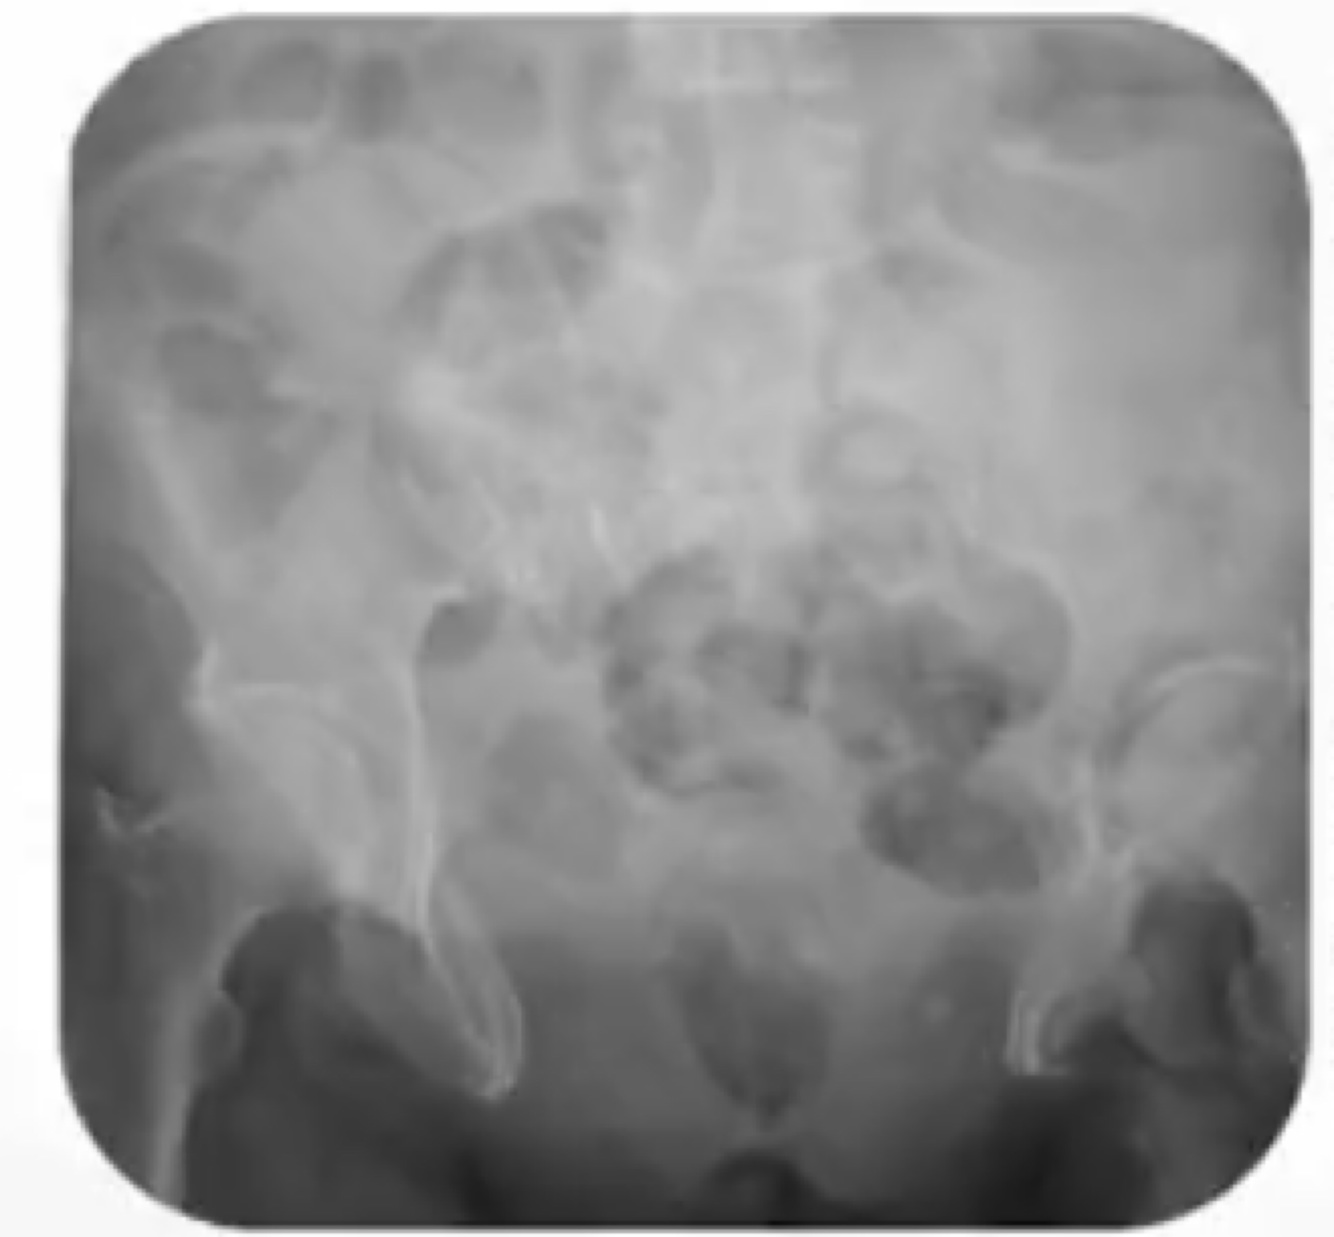

Achado da imagem e dois diagnósticos possíveis:

Diástase de sínfise púbica.

Epispádia ou/e extrofia de bexiga.